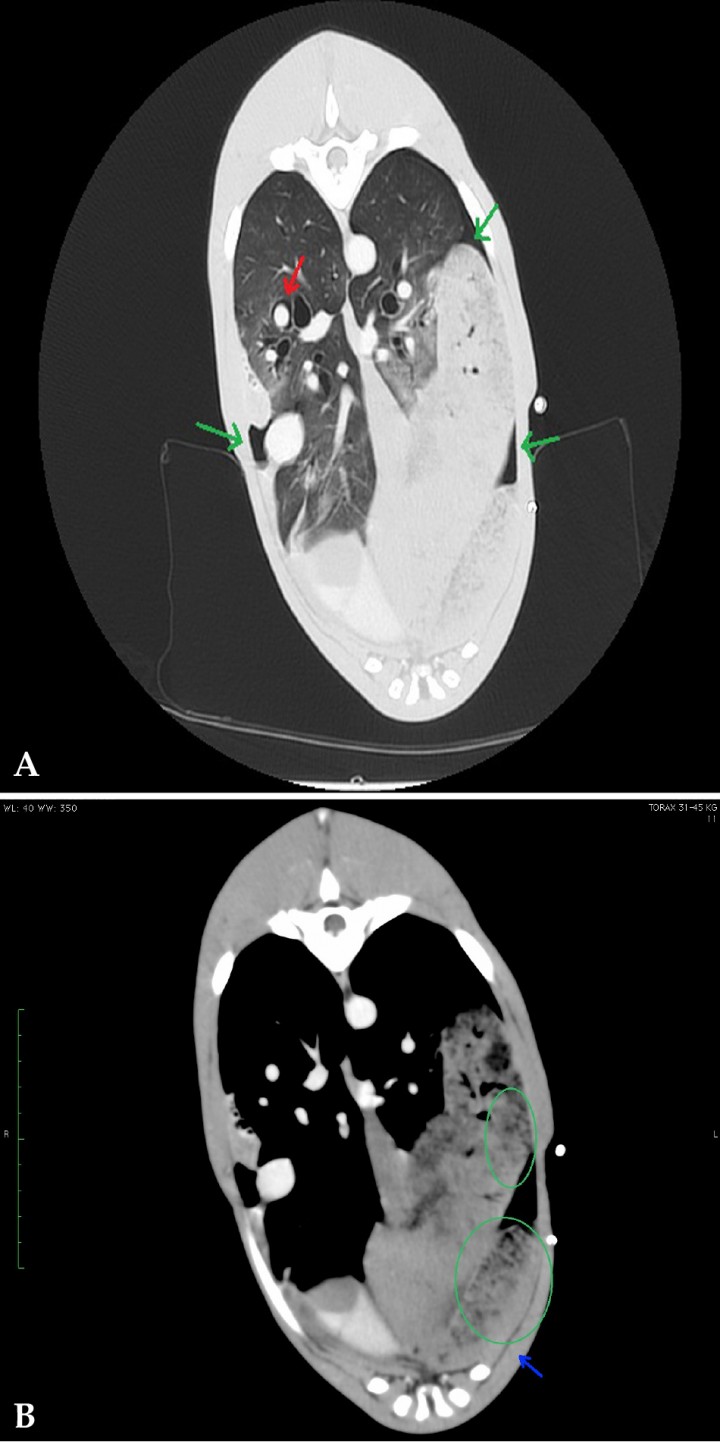

Figura 5

(A) Corte transversal en ventana pulmón. (B) Corte transversal en ventana tejido blando. Lóbulo pulmonar torsionado (flecha azul) con patrón vesicular visible en la porción caudal del lóbulo craneal izquierdo (círculo verde). Pequeño volumen de aire en espacio pleural (flechas verdes) y de enfisema intersticial alrededor de la arteria pulmonar del lóbulo caudal derecho (flecha roja).